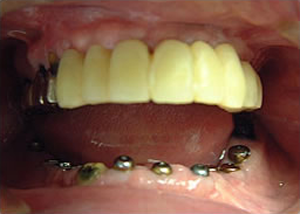

14.上は作った最終本物の歯が入っています。

下はチタンの土台が10本入りました。

16.上は仕上がりが入り、下は仮歯です。

19.下は作った最終本物の歯が入りました。

これで治療終了。

開口器を入れた口元

治療完了

平成21年1月29日

(治療期間:1年7ヶ月)